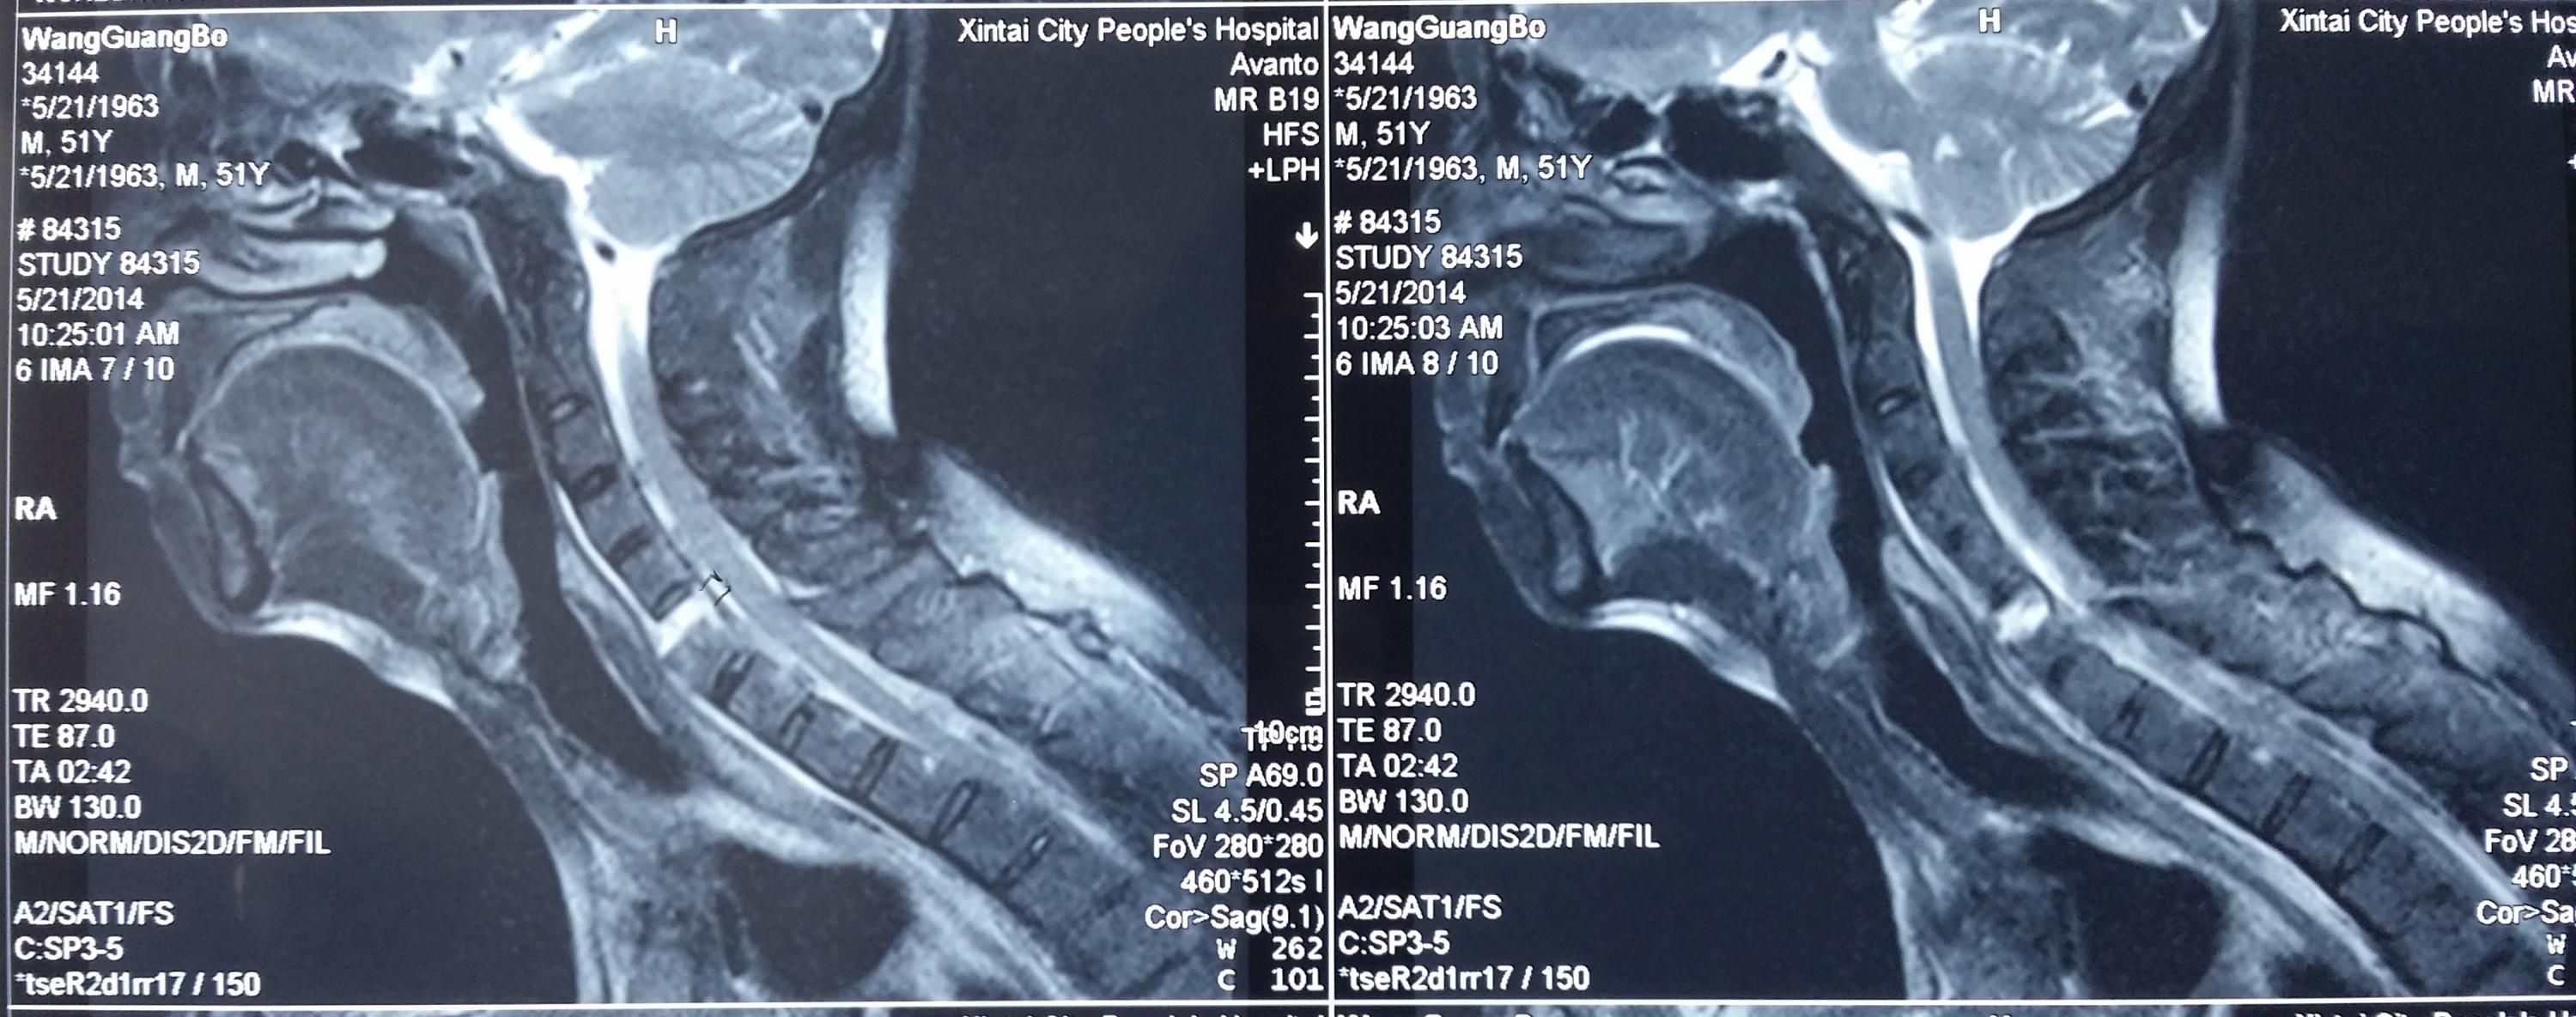

病人王某,男性,51岁,因“颈背部外伤后疼痛、双手麻木3小时”入院。系摩托车撞伤,先后咨询我市多家医院,均不敢收治。入院时病人双手中指、食指麻木,双上肢肌力Ⅲ级,双下肢肌力Ⅳ级。CT检查显示:颈5、6椎体及附件爆裂骨折、脱位并椎管狭窄,强直性脊柱炎。颈椎磁共振检查显示:颈髓受压,髓内未见明显高信号。我院即刻给予颈托外固定,完善术前检查,给予颈椎前路植骨融合内固定术,术后恢复好,术后影像复查显示骨折解剖复位,病人无不适感觉,行走同受伤前,20天后痊愈出院。

强直性脊柱炎的病理变化包括脊柱骨性强直、椎体骨质疏松等,导致脊柱骨脆性增加,较常人更容易发生骨折,该类骨折的损伤机制多属过伸伤,颈胸腰段均可发生,可导致四肢瘫、截瘫,致残率极高,死亡率高,对病人、家庭是巨大的灾难。高颈椎椎体骨折治疗风险高,技术难度大,一般医疗单位不愿意承担如此高风险的挑战。对该病人计划采用前后路联合固定治疗,因强直性脊柱炎所致的胸椎后突畸形显著,手术体位摆放困难,仅进行了前路植骨融合手术,术后强化颈托固定,以利骨性愈合。目前病人手术后三个月,复查CT显示:骨折解剖复位,有骨痂生长,无不良感觉,行走自如,与受伤前相比没有不适,劳动能力完全恢复,实现了回归社会的最好要求。

图二:颈托固定后MRI片